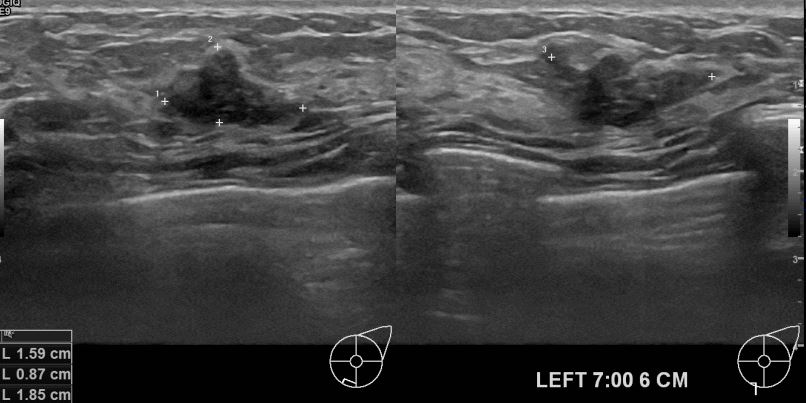

아산유외과 개원후 602번째 유방암 진단

상기환자 왼쪽가슴의 딱딱해지는 멍울있어 내원하신 30대 여성분으로 초음파검사후 의심스러운 혹 조직검사진행해 유방암 진단되었읍니다.